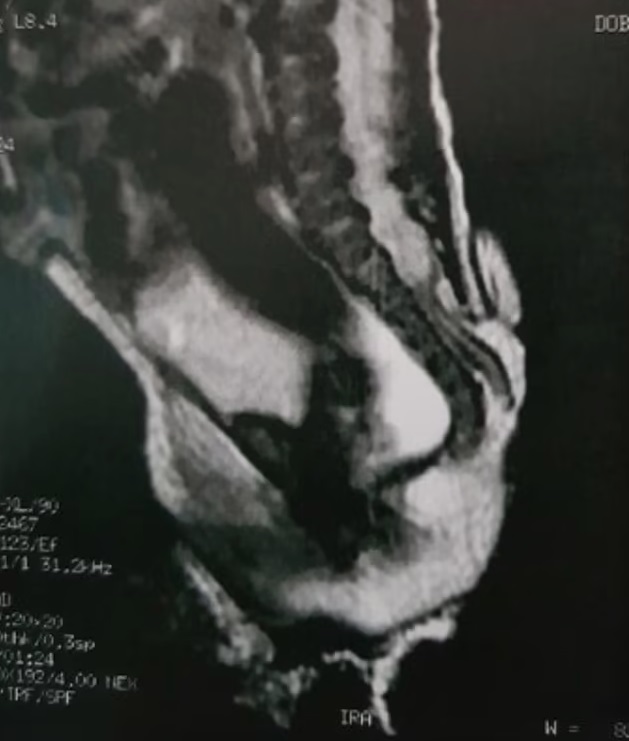

ولدت الفتاة التي لم تذكر التقارير هويتها، مصابة بـ”السنسنة المشقوقة”، وهي عيب خلقي نادر في العمود الفقري يحدث في الرحم، ويسبب فجوة في العمود الفقري.

وتمكن الجراحون من إزالة الذيل وإغلاق الفجوة في العمود الفقري. وكشف الأطباء من GRENDAAC، وهو مستشفى للأطفال في ساو باولو، إن الذيل انتشر من المنطقة القَطنية العجزية، المنطقة التي تربط العمود الفقري بالحوض.

وشخص الفريق هذه الأنسجة الزائدة على أنها “ذيل بشري زائف” (pseudo-tail)، وهو نمو يشبه الذيل ولكنه ناتج عن مشاكل العمود الفقري أو الأورام.

ودرس باحثون من مركز أبحاث الجنين والمشيمة في أوهايو الحالة إلى جانب الأطباء البرازيليين. وكتبوا: “الزوائد الذيلية البشرية هي آفات نادرة تفرض وصمة عار كبيرة على حامليها وأولياء أمورهم. وترتبط الزوائد الذيلية الجنينية بخلل العمود الفقري (السنسنة المشقوقة)، وبالتالي فإن وجودها يتطلب فحصا دقيقا لعيوب الحبل الشوكي الكامنة. إن تحديد العديد من الحالات الشاذة المرتبطة المحتملة أمر بالغ الأهمية لتخطيط العلاج الصحيح وتقديم مشورة جيدة”.